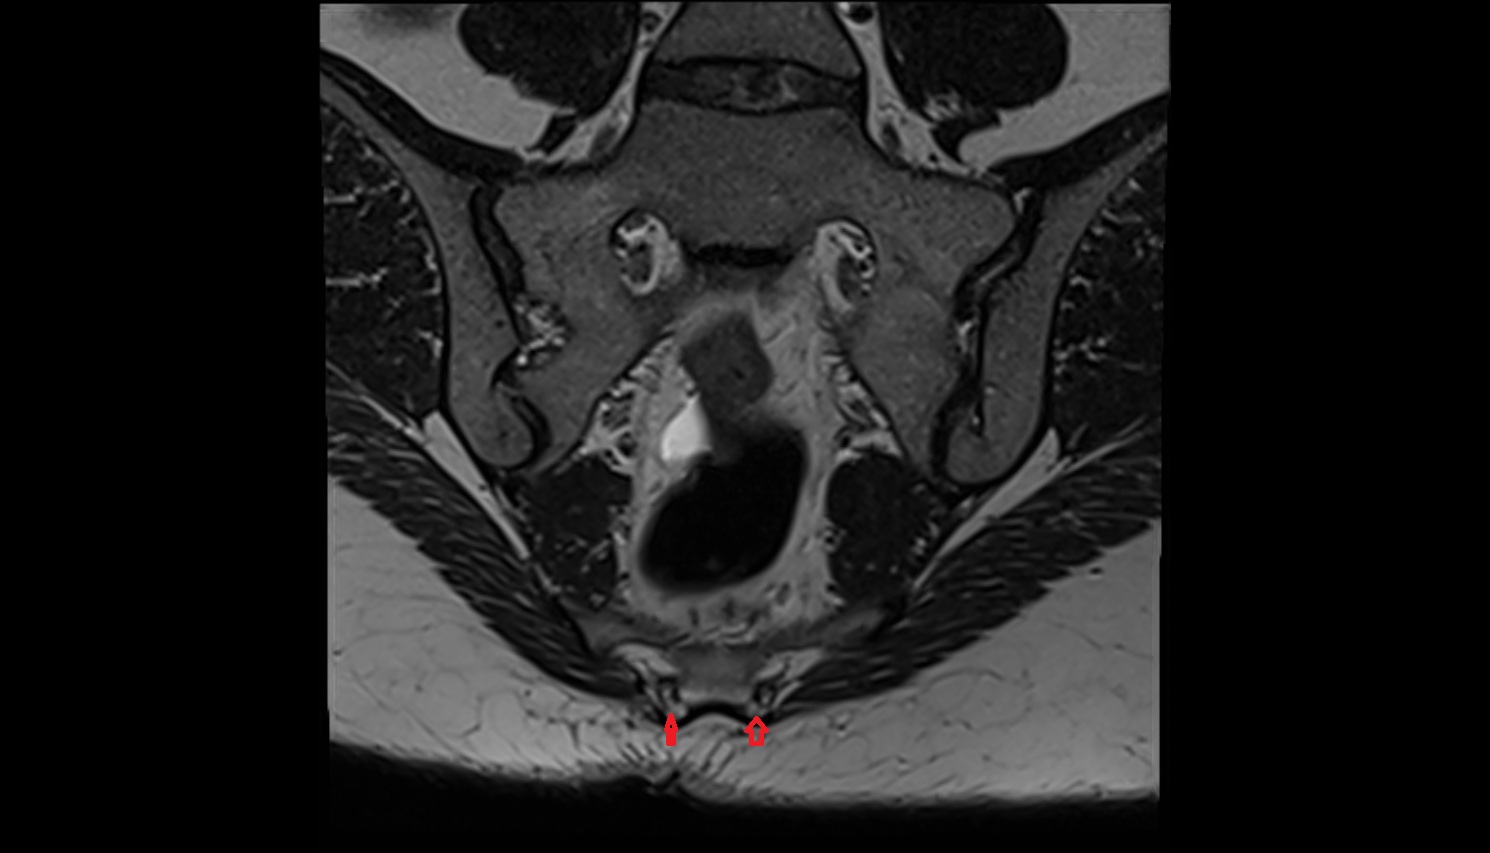

- Pubic symphysis